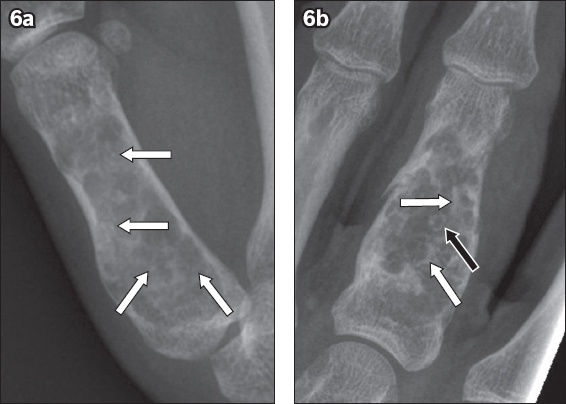

Fig. 6

(a) Frontal radiograph of an enchondroma in the right thumb proximal phalanx of a 24-year-old with ‘dot-like’ or ‘stippled’ matrix calcifications (arrows). (b) Frontal radiograph of an enchondroma in the left middle finger proximal phalanx of a 52-year-old man with ‘ring’ (black arrow) and ‘arc’ (white arrows) matrix calcifications.